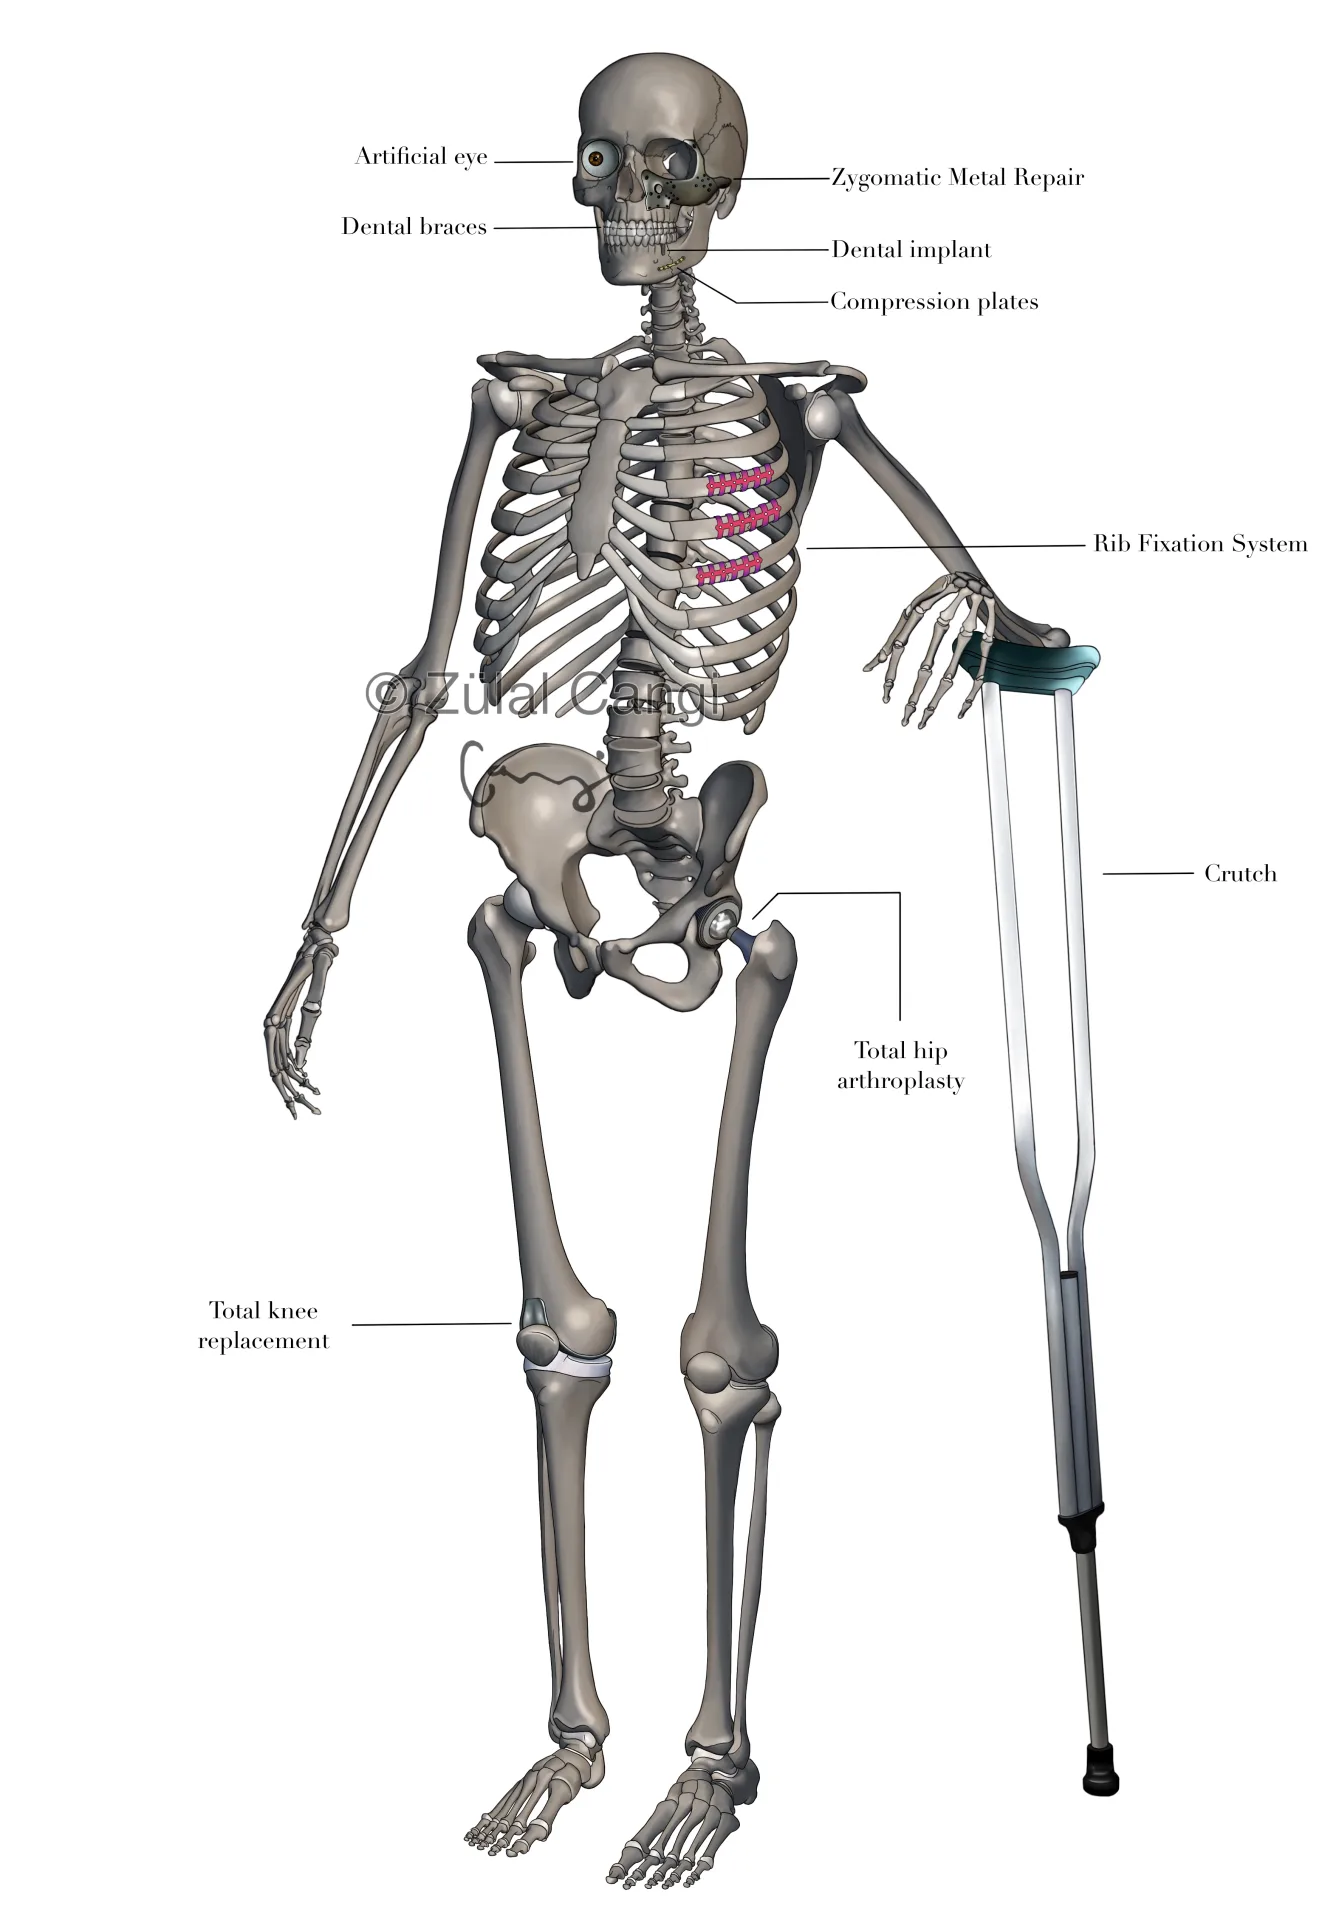

Sanatın estetiğini bilimin kesinliğiyle bir araya getiren Zülal Cangi, medikal ve bilimsel illüstrasyon alanındaki çalışmalarıyla akademik yayınlar, eğitim materyalleri ve çeşitli bilimsel platformlar için görsel içerikler üretmektedir. Amacı, bilimsel bilgiyi yalnızca doğru biçimde aktarmakla kalmayıp, aynı zamanda öğretici ve estetik bir dille görünür kılmaktır.

PORTFÖY